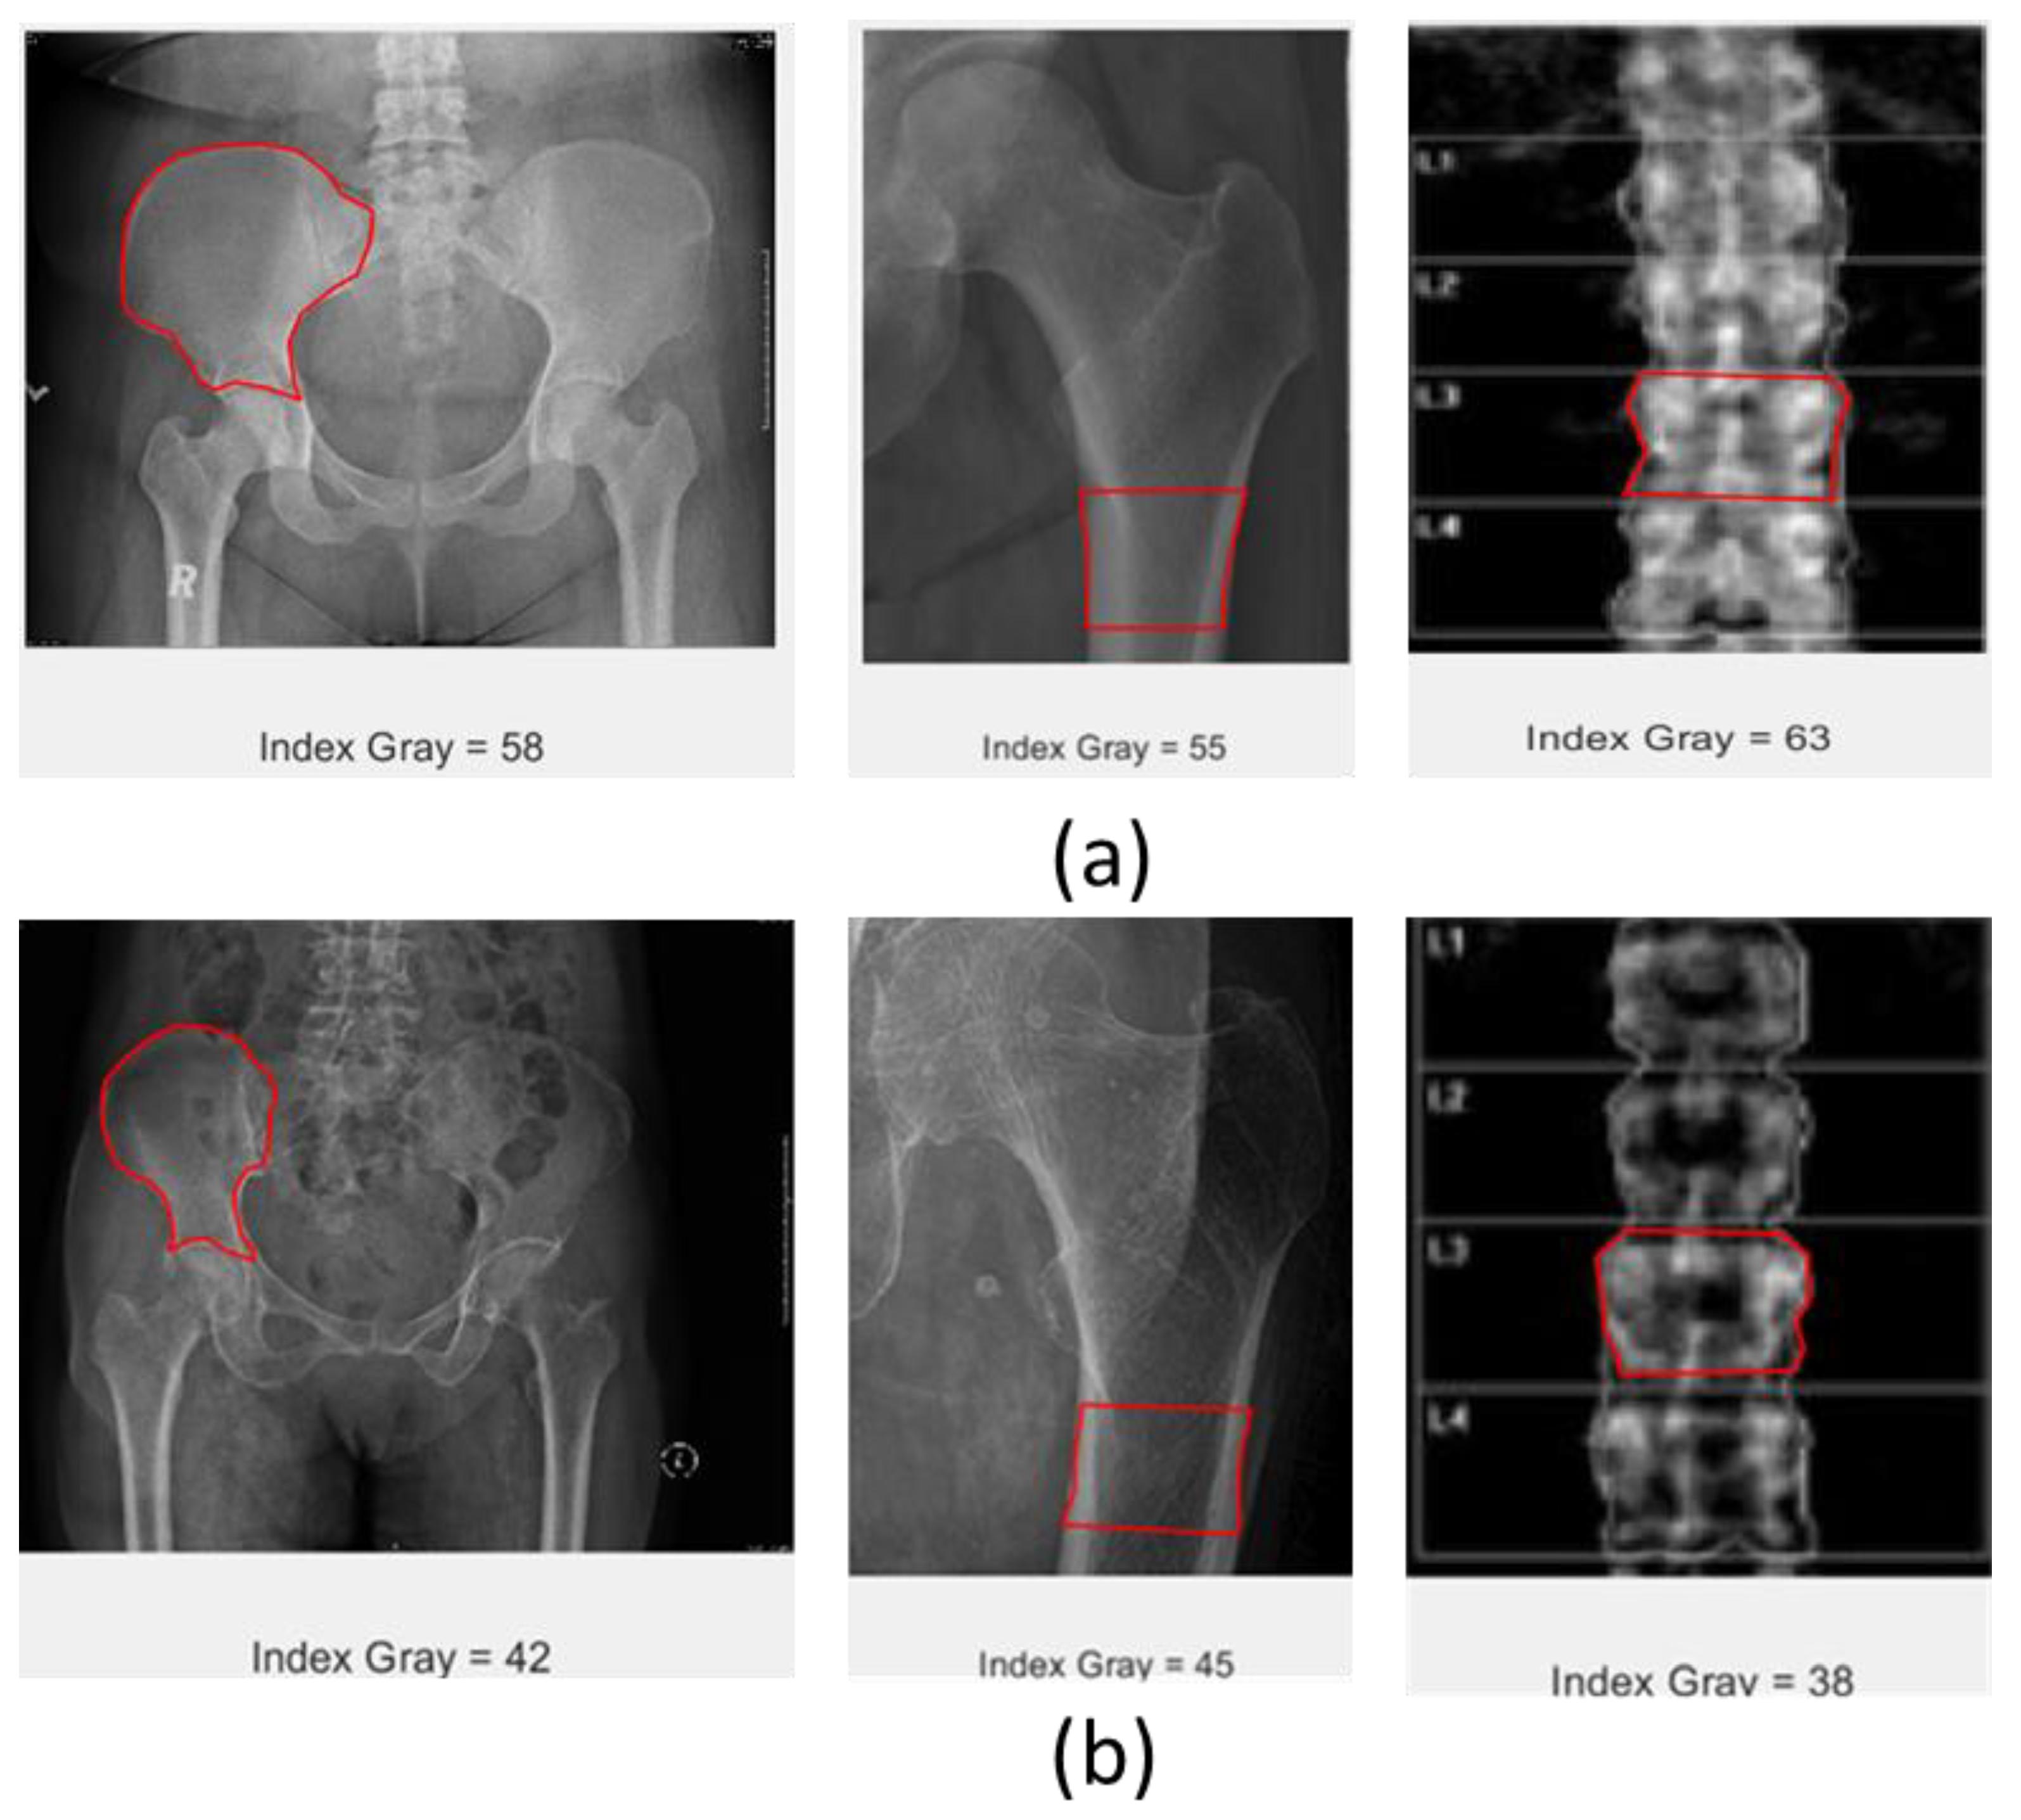

5.1. Grayscale Index

The grayscale index is calculated based on the total grayscale value inside the ROI divided by the total pixels of the ROI. The grayscale value indicates the hardness of the tissues; if tissues are hard, they will be displayed as white, while the soft ones will be darker. The grayscale value is equivalent to amplitude values in the time series signal, and in this case, shows the intensity of the CT scan image of the object. Grayscale index values for patients with normal bone are expected to be higher than those of osteoporosis patients.

Figure 3 illustrates the data sets from the experiment. Data sets consist of CT scan data of the pelvic and hip, and DEXA scans of the lumbar spine. The X-ray energy used for CT scanning is 400 times higher than that used in DEXA scanning. The result showed that the grayscale value tends to decrease from normal to osteoporosis bone, and the difference is quite significant. As expected, healthy bone is harder compared with osteoporotic bone; thus, its appearance upon X-ray scanning will be displayed as brighter than osteoporosis. The grayscale index consistently decreases in both CT scans and DEXA images from normal to osteoporotic bone.

Figure 3. Grayscale index of different image data of pelvic (left), hip (middle), and lumbar spine (right); (a) normal bone and (b) osteoporotic bone, red box indicates a selected ROI.